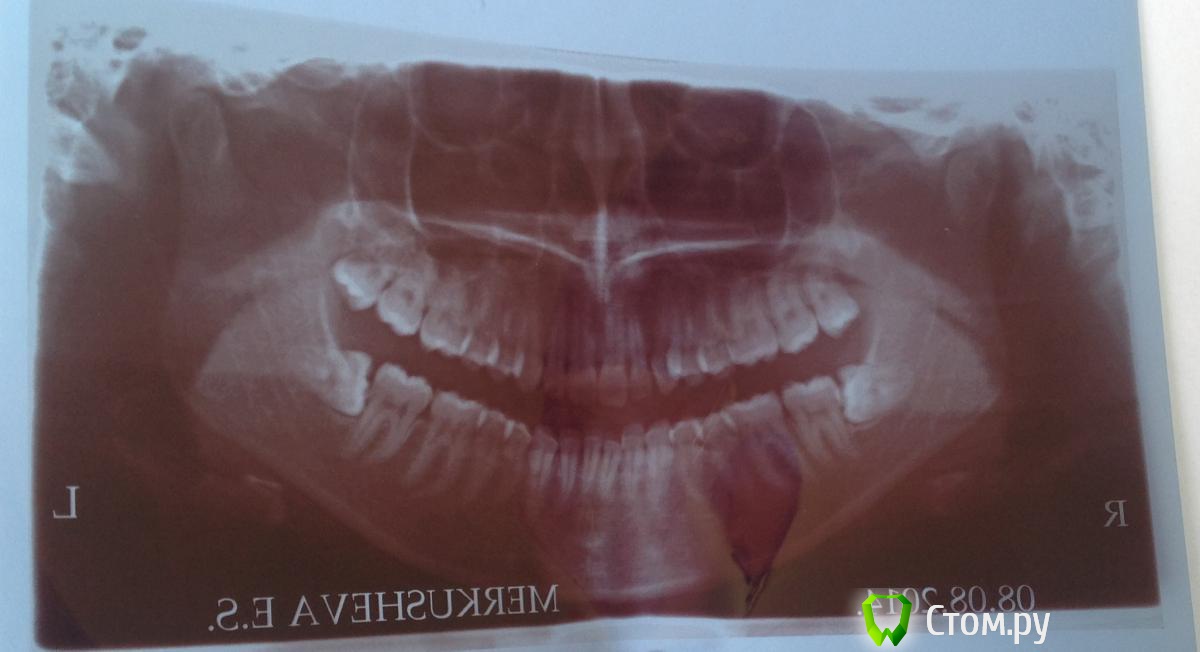

Елена11 Опубликовано 29 августа, 2014 Поделиться Опубликовано 29 августа, 2014 Здравствуйте, уважаемые стоматологи!Вопрос об удалении нижних ретинированных дистопированных зубов мудрости. 1) Врач городской поликлиники объяснил, что зубы расположены близко к нижнечелюстным нервам, в связи с чем есть опасность потери чувствительности или даже подвижности нижней челюсти, и дабы избежать подобного, направил меня в Московскую Областную Стоматологическую поликлинику. Сказал, что у них есть необходимая аппаратура, и что меня там положат в стационар. 2) в МОСП меня встретила молодая врач, которая сказала, что в стационар класть не будут, и по поводу возможности задеть нерв: «я не могу обещать, что не задену нерв, но потери подвижности не будет точно». При этом она сказала, что кроме имеющегося у меня снимка никаких обследований делать не нужно.Для меня непонятно, то ли первый врач излишне меня запугал, то ли вторая отнеслась несерьезно.Разумно ли в данной ситуации обойтись без госпитализации, есть ли необходимость проводить какие-то обследования кроме имеющегося снимка, и могут ли эти 2 операции быть проведены в обычной стоматологической поликлинике, просто у хирурга, которому я как врачу буду доверять, или стоит поискать какое-то специфическое мед. учреждение? Если да, посоветуйте, пожалуйста, подобные учреждения в Москве. Ссылка на комментарий

dr-krasnov Опубликовано 29 августа, 2014 Поделиться Опубликовано 29 августа, 2014 Не увидел ничего особенного. Сделайте КЛКТ для уточнения топографии и все будет хорошо, уверен. Ссылка на комментарий

red_butler Опубликовано 29 августа, 2014 Поделиться Опубликовано 29 августа, 2014 При квалифицированном подходе абсолютно рутинные удаления. Стационар не нужен, в идеале удаление под седацией. Ищите хирурга. Загляните во врачебный хирургический раздел, и поймете, что ваши зубы не такие уж и "страшные"По поводу потери чувствительности, всегда возможные осложнения оговариваются до а не после лечения. Вероятность подобного в вашем случае - низкая 3 Ссылка на комментарий